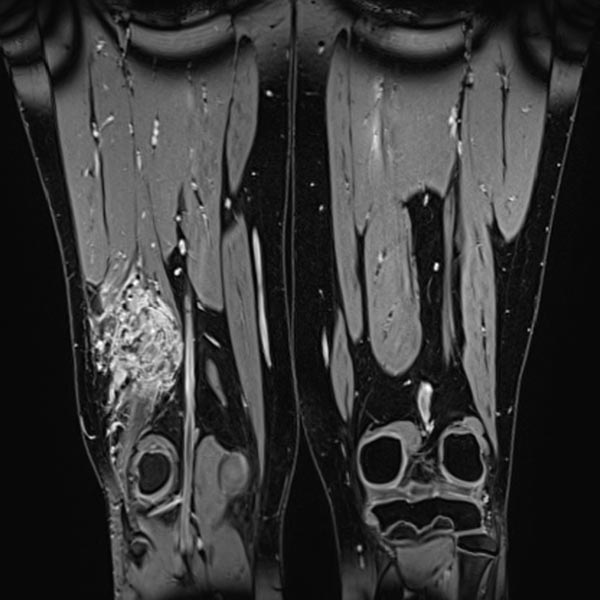

Coronal fat-suppressed T2-weighted MRI of the thighs shows an intramuscular venous malformation on the right thigh (hyperintense).

T2-weighted MRI without fat suppression in the axial plane reveals inflammatory, fibrotic remodeling of the lesion due to multiple inflammations. The right vastus lateralis of the quadriceps femoris muscle is completely penetrated by the lesion.